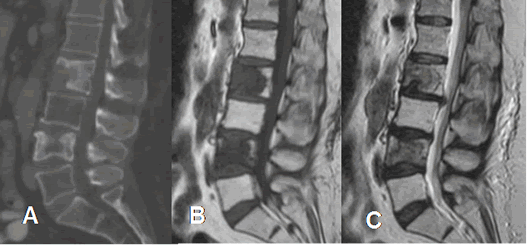

Fig 15. Tumor fibroso.

A: TAC reconstrucción sagital. Cuerpos de L2 y L4 escleróticos y con lesiones líticas,

por metástasis de próstata.

B: RM sagital en T1 y C: RM sagital en T2. Las lesiones son hipointensas en T1 y T2, por el alto contenido fibroso.